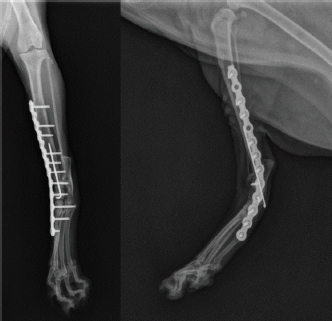

An 18-month-old female stray European cat was referred to the Veterinary Teaching Hospital of the University of Camerino, Italy. Anamnestic data reported a distal tibial epiphyseal sliding fracture (SH1) of the right hind limb inadequately treated 8 months prior with an intramedullary pin by colleagues and consequent chronic tarsocrural instability. Gait evaluation showed a non-weight bearing lameness (grade 4/5) of the right hind limb. An orthopedic examination revealed severe pain during the manipulation of the right tarsus, with bone crackling during stressed manipulation elicited by tibiotarsal joint laxity. Mediolateral and craniocaudal projections of the right tarsus showed failure of the fracture implant (intramedullary pin) caused by an inadequate choice of the apparatus and an incorrect osteosynthesis technique, with a caudomedial displacement of the right distal tibial epiphysis and a moderate process of bone remodeling and resorption (Fig. 1). The patient underwent pantarsal arthrodesis for the recovery of limb functionality. The anesthetic protocol included premedication with 3 μg/kg of dexmedetomidine (Dexdomitor 0.5 mg/ml; Orion Corporation, Finland), 0.3 mg/kg of methadone (Semfortan 10 mg/ml; Dechra, Italy), and 3 mg/kg of ketamine (Ketavet 100; Intervet Productions s.r.l., Italy) administered intramuscularly (IM). General anesthesia was induced with 4 mg/kg of propofol (Fresenius Kabi, Isola della Scala, Italy) administered intravenously (IV) and maintained with oxygen and isoflurane. When a good anesthesia plan was achieved, the femoral–sciatic nerve block was carried out with 0.2 ml/kg of lidocaine (Xylocaine 2%; Zidus Cadila, India). The affected limb and the contralateral foreleg were clipped, and a 4% chlorhexidine gluconate detergent was used for the preliminary preparation of the surgical sites, with a minimum contact time of 5 minutes. The patient was positioned in right lateral recumbency, with the affected limb toward the operating table and the contralateral limb fixed in the abduction position. Cefazolin (Cefazoline Teva; Teva s.r.l., Italy) was administered IV (22 mg/kg) approximately 30 minutes before the skin incision. Under complete aseptic precautions, the craniomedial approach was carried out to expose the tarsal joint. A skin incision, the same length as the plate, was made on the caudomedial aspect of the distal tibia and the craniomedial aspect of the tarsus and proximal metatarsus. The intramedullary pin was removed and sent to the laboratory for bacteriological examination. The tarsocrural, intertarsal, and tarsometatarsal joints were exposed, and the articular cartilage was removed with a high-speed burr. The autologous bone graft was collected from the cancellous bone of the contralateral humerus and was subsequently inserted into the joint spaces. After joint reduction, pantarsal arthrodesis was performed. A 1.2-mm Kirschner wire was driven through the calcaneus into the tibia, and a Compact UniLock 2.0 mandible locking plate (DePuy Synthes, Oberdorf, Switzerland) of 1.5-mm thickness was contoured to achieve the functional angle of tarsus extension and was positioned on the medial surface of the tarsus (Fig. 2). The plate was fixed with ten 2.0 mm locking screws and a cortical screw. The soft tissues were sutured by planes using a USP 3/0 absorbable monofilament thread. No tension at the suture lines was observed. The surgery lasted for 63 minutes. At the end of the surgery, an X-ray examination (Fig. 3) showed a good apposition of the fracture, with a slight internal rotation of the calcaneus; the apparatus seemed adequate, with a total plate screw density (PSD) of 0.85. The joint was fixed at 137° in extension. After radiographic examination, a soft padded bandage was applied for 14 days, which was renewed weekly. As needed, 0.3 mg/kg of methadone (Semfortan 10 mg/ml; Dechra, Italy) was administered IM for 24 hours postoperatively. Anti-inflammatory therapy (meloxicam 0.05 mg/kg; Metacam 40 mg/ml; Boehringer Ingelheim Vetmedica, Germany) and ranitidine (2 mg/kg; Zantadine 30 mg/ml; Ceva s.p.a., Italy) IV were administered on an inpatient basis. The first orthopedic evaluation, the first day after surgery, showed an improvement in gait (grade 2/5 of lameness on walk). The cat was discharged from the hospital after 3 days with a prescription of anti-inflammatory and analgesic therapy. The head of the cat shelter was instructed to subject the cat to cage rest for 30 days. At the first follow-up, 7 days after surgery, the soft padded bandage was renewed, and the cat showed a steady improvement in gait. Fourteen days after surgery, the soft bandage was removed; the orthopedic examination showed mild improvement in gait, although second-degree lameness and an extended tarsal and flexed stifle gait persisted because of the arthrodesis procedure. No swelling or dehiscence at the surgical site or skin tension under the plate was observed; the suture was removed, and the cat was discharged with light exercise on a larger cage recommendation for the remaining 15 days. One month after surgery, at the orthopedic evaluation, the head of the cat shelter reported a slight worsening of lameness after a sharp jump had occurred 7 days prior. The patient showed good limb function, with a slight worsening of gait during the trot, and the radiographic evaluation showed good bone activity, with 50%–66% of the joint fusion and fracture healed, although a metatarsal stress fracture was revealed (Fig. 4). Four months after surgery, radiographs revealed stable implants and an almost complete fusion of the joints (Fig. 5). The surgical wound site, 30 and 120 days after surgery, healed very well, with an efficient aesthetic result of the limb, even with a slight loss of skin elasticity, which occurs naturally after surgery. The patient never showed discomfort at the implant site, even though the plate was very superficial and palpable under the thin skin (Fig. 6). Moderate free activity with gradual introduction to freedom in the feline colony was prescribed.

Fig. 1. Craniocaudal and mediolateral radiographs of right tibia and tarsus showing an inveterate articular fracture of right distal tibial epiphysis with cranial displacement, previously treated with an intramedullary pin (see arrows). The pin does not engage the proximal portion of the tibia and runs for almost its entire length in the caudal portion of the leg.